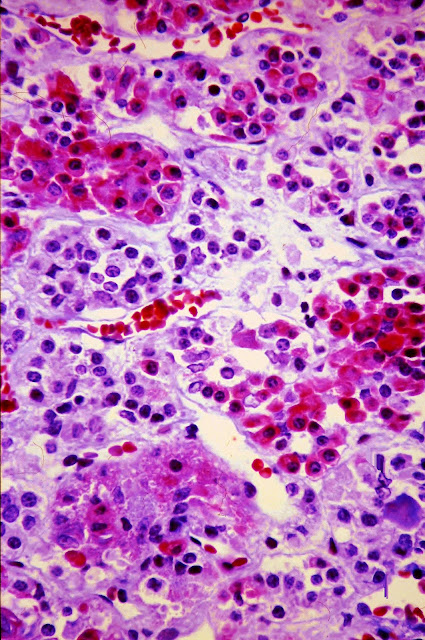

Las fotografías que se muestran a continuación pertenecen al estudio microscópico del pulmón. El cuadro morfológico es similar en todas ellas y consiste en la presencia de hemorragias alveolares multifocales y de trombos plaquetarios, en algunos casos ocluyentes. En algunos cortes se detectó, también, la presencia de embolización por médula ósea (con megacariocitos), hallazgo muy frecuente en los cadáveres de pacientes que han sido sometidos a maniobras de resucitación cardiopulmonar.

Fig. 7.-Pulmón.Microscópico.

Corte longitudinal de un vaso cuya luz aparece ocupada por trombos, no ocluyentes, formados, exclusivamente, por plaquetas. Prof.Garfia.A

Fig. 8.-Pulmón.-

Detalle de los trombos plaquetarios flotando en el seno de la columna eritrocitaria, compactada (sludging). Prof.Garfia.A

Fig. 9.-Pulmón. Microscópico.

Trombo plaquetario ocluyente ocupando la luz de un vaso de mediano calibre. Prof.Garfia.A

Fig. 10.-Pulmón. Microscópico.

Trombo plaquetario ocluyente en el que se aprecian líneas formadas por la agregación plaquetaria. Nótese la ausencia total de fibrina que se tiñe de rojo con la coloración tricrómica, tal como se observa en el caso 108.5.

Fig. 11.-Pulmón.

Trombos plaquetarios, de tipo ocluyente, asociados a microinfartos hemorrágicos. Prof. Garfia.A

Fig. 14.-Pulmón.Detalle de un trombo plaquetario ocluyente. Prof.Garfia.A

Fig. 15.-Pulmón.

Corte longitudinal de un vaso ocupado por un trombo plaquetario ocluyente. Prof.Garfia.A

Fig. 16.-Pulmón. Trombos plaquetarios ocupando parcialmente los vasos. Prof. Garfia.A